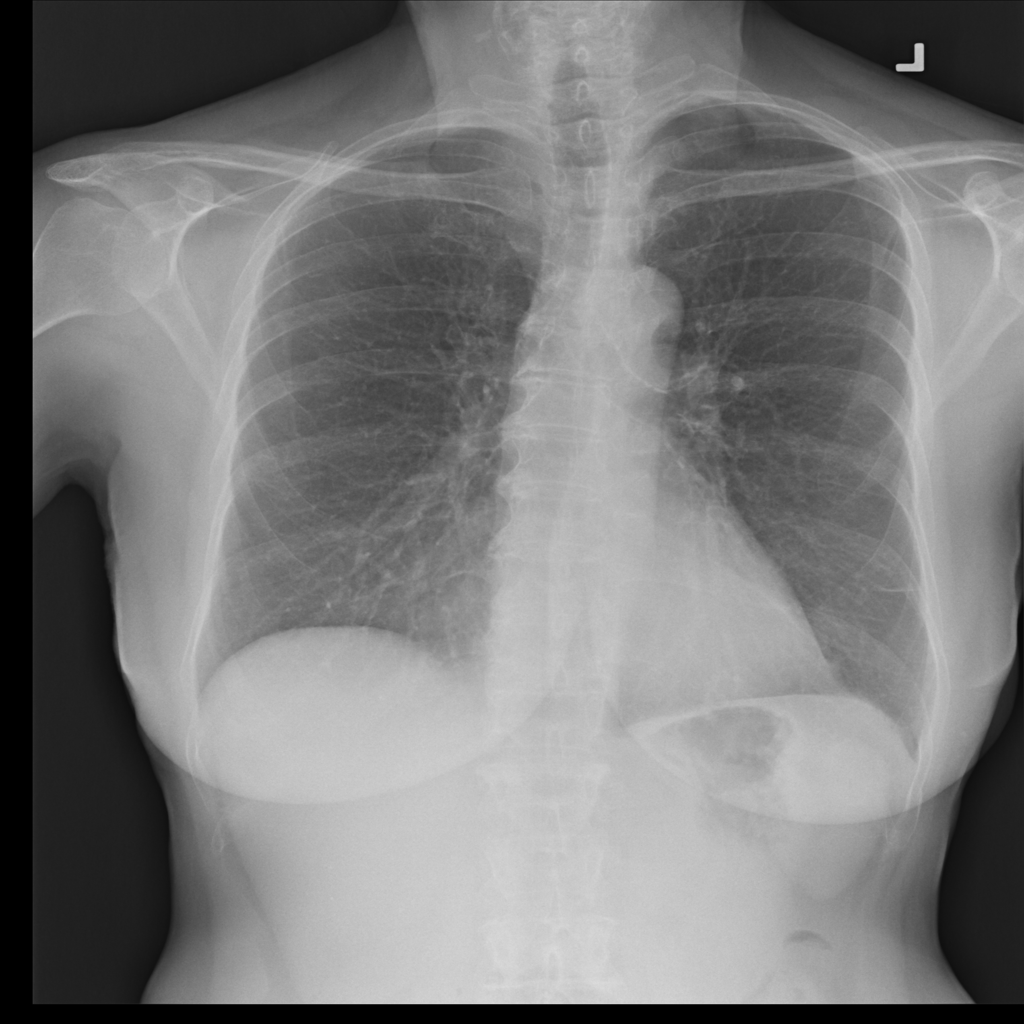

PAT-86C8 · IMG-006Atelectasis

PAT-86C8 · IMG-006

PA